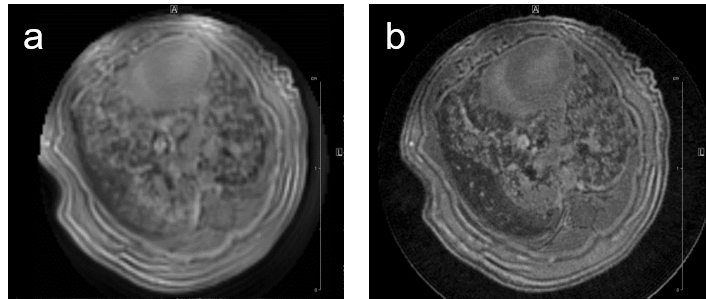

MRI may be used to quantitatively measure lung tumor burden and to follow up e.g. tumor growth. Images of a transgenic mouse model of hyperproliferation in the lung show clearly the replacement of the lung parenchyma Fig. 5.

Fig. 5: Mouse lung MRI. Exemplary axial MR-images of a mouse lung with hyperplasia: (a) respiratory-gated UTE-3D sequence with a repetition time of 8.0 ms, echo time of 20 µs, slice thickness/interslice distance: 0.39/0.39 mm, field of view 2.50x2.70x5.00 cm3 and a matrix of 128/128/128 and (b) respiratory-gated ZTE-3D sequence with a repetition time of 4.0 ms, echo time of 0 µs, slice thickness/interslice distance: 0.16/0.16 mm, field of view 3.00x3.00x4.00cm3 and a matrix of 256/256/256.